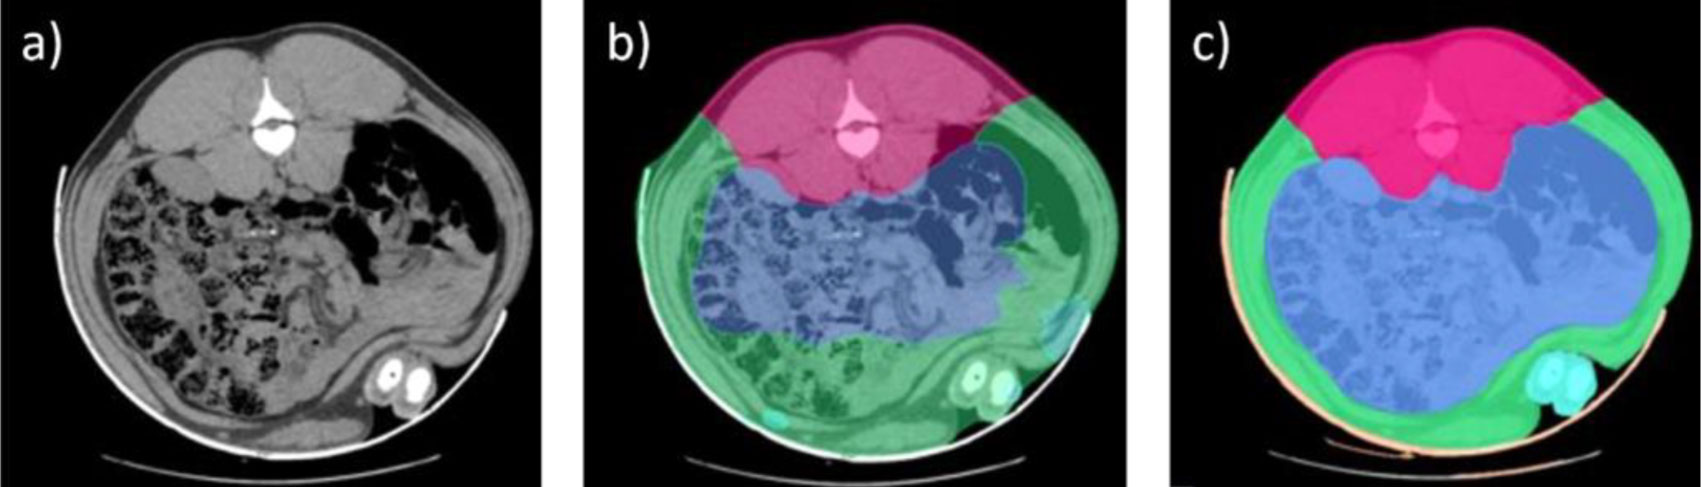

Przez lata analiza obrazów była wykonywana ręcznie, identyfikując różne obszary anatomiczne i typy tkanek (kości, tłuszcz i mięśnie), co już stanowiło znaczący postęp. W 2016 roku wdrożono bardziej zautomatyzowaną metodę analizy obrazów TK, umożliwiającą rozróżnienie różnych głównych kawałków mięsa (szynka, łopatka, schab i boczek). Pojawienie się technologii sztucznej inteligencji (AI) miało kluczowe znaczenie dla automatyzacji tego procesu, co było niezbędne do zwiększenia skali stosowania tego narzędzia i zwiększenia liczby analizowanych zwierząt w bardziej efektywny sposób.

Jednak AI wymaga wcześniejszego procesu szkolenia, co wymaga ogromnej bazy danych wcześniej analizowanych obrazów, które służą jako modele. W naszym przypadku baza danych była dostępna dzięki wieloletniej analizie tomografii komputerowej, podczas której osiągnięto już znaczny postęp w segmentacji tkanek i identyfikacji wokseli (najmniejszych jednostek tworzących trójwymiarowy obraz, podobnych do pikseli na fotografii) należących do różnych tkanek.